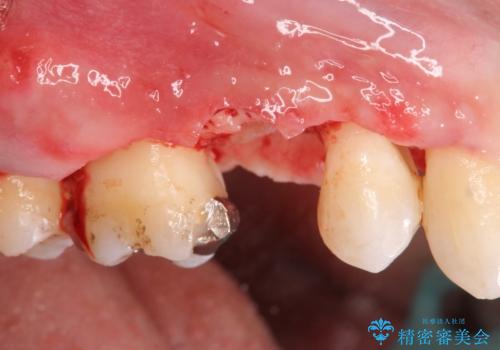

検査をしたところ、右上小臼歯に破折が見られ保存が難しい状況です。

抜歯を行い、咬合機能の回復を行いますが、咬合関係や非常に強い噛み合わせの問題をふまえ、咬合面をメタルにしたメタルボンドブリッジで治療を行うこととしました。

また噛み合わせが深くブリッジの強度が十分に確保できないことから、抜歯時に歯周外科を行うことで十分に安定したクラウン装着をできるような処置を行っています。